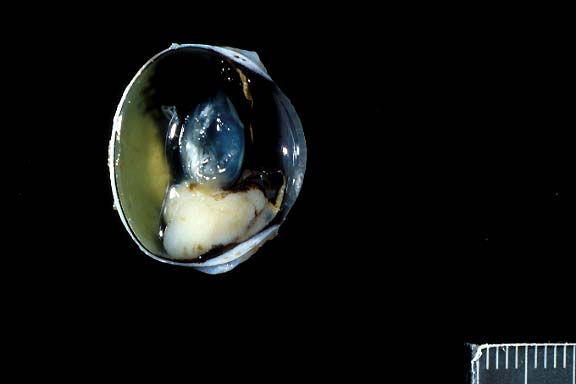

- Gross Pathology: An irregularly shaped, pale tan mass

the globe and extended caudally from the iris.

- Contributor's Diagnosis and Comments: Eye: Iridociliary

- A partially encapsulated, highly cellular mass consisting

of cuboidal to polygonal cells arranged in loose cords, packets,

and occasional rosettes is adherent to the posterior aspect of

the iris and to the ciliary body. The neoplasm infiltrates the

base of the iris and extends into the filtration angle. Irregularly

shaped, dilated channels are present in some areas, and the mass

is supported by a fine fibrovascular stroma. Cells within the

mass have large, round to oval, occasionally indented nuclei,

1-2 nucleoli, finely stippled chromatin, small to moderate amount

of foamy, eosinophilic cytoplasm, and variably-distinct to indistinct

cell margins. A few cells have large, irregularly shaped nuclei,

and the mitotic rate varies from 0-3 per high-powered field.

Some scleral vessels adjacent to the neoplasm contain thrombi

and seemingly have "infiltrates" of cells (may not

be visible in all sections); the cells are dissimilar to those

within the neoplasm and may, in fact, represent a reaction to

thrombosis or other negative vascular events.

2x

obj

- Case 12-3. Eye. A monomorphic mass replaces the iris.

- AFIP Diagnosis: Eye: Ciliary body adenocarcinoma,

Domestic Longhair, feline.

- Note: some sections contain minimal cataractous change.